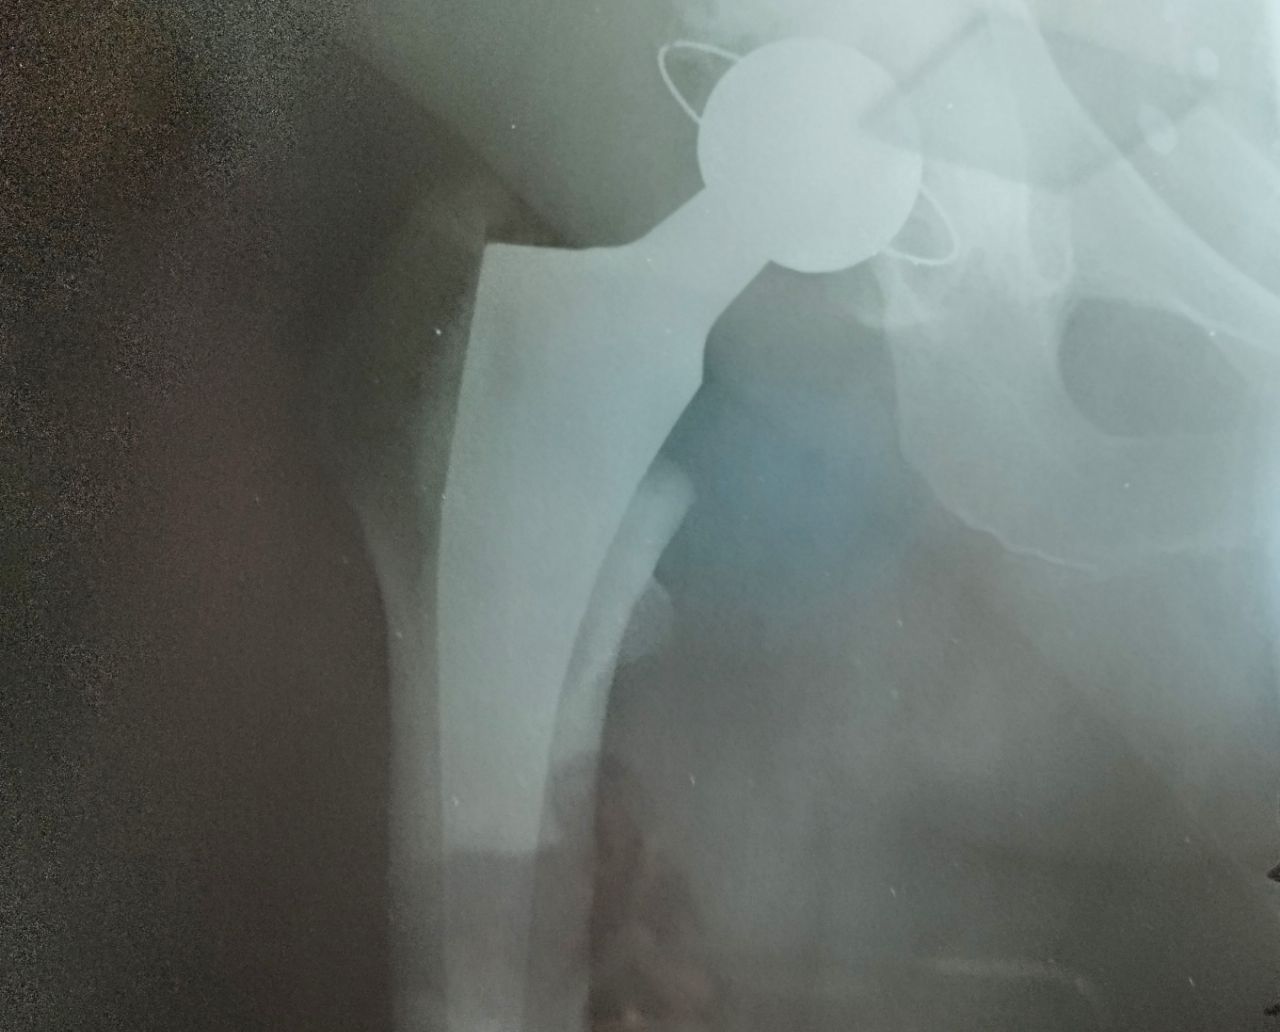

Титановый эндопротез

Какое это чудо - титановый сустав.